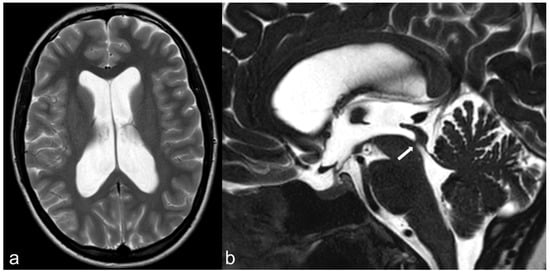

3.1.2. Optic Nerve (II) and Orbital Masses

3.1.3. Ocular Motor Nerves (III–IV–VI)